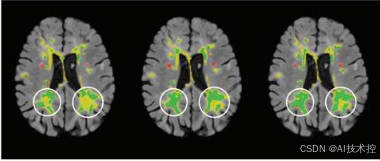

医学图像是现代医学诊断的重要工具,广泛应用于疾病检测、治疗规划和手术辅助。然而,在实际应用中,医学图像常因噪声、伪影、数据丢失等问题导致质量下降,影响诊断的准确性和医疗决策的可靠性。如何高效且精准地修复医学图像,成为了一个重要的研究课题。

医学图像修复的目标是从受损或低质量的医学图像中恢复出高质量的原始图像。然而,医学图像修复面临以下挑战:

- 噪声干扰:例如,低剂量CT图像中常见的高噪声会影响影像细节。

- 伪影问题:MRI图像中的运动伪影或金属植入物引起的伪影会导致图像失真。

- 数据缺失:部分医学图像可能因遮挡、扫描不完整或设备故障而缺失部分区域。

- 高分辨率需求:医学图像需要高分辨率以呈现微小病变,为诊断提供可靠依据。

医学图像修复是医学图像处理中的重要任务,旨在从噪声、伪影或缺失区域中恢复高质量的图像。近年来,生成式模型(Generative Models)在这一领域取得了显著进展,变分自编码器(Variational Autoencoders, VAEs)、对抗生成网络(Generative Adversarial Networks, GANs)和扩散模型(Diffusion Models)是其中的三大代表。每种模型都有其独特的原理和优势,在医学图像修复中展现出不同的应用潜力。